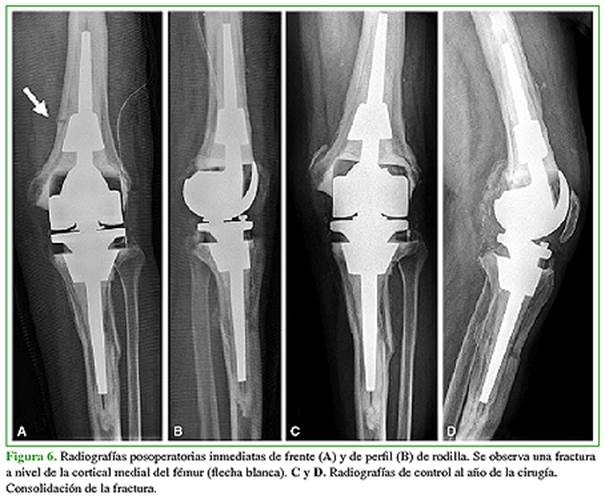

La tasa de complicaciones fue del 20% (n = 7) y la de reoperaciones, del 8,5% (n = 3). Durante la cirugía, dos pacientes presentaron una fractura periprotésica incompleta de fémur (tratadas, de manera conservadora, con consolidación ósea en el seguimiento) (Figura 6). Se registraron cuatro complicaciones posoperatorias: un caso de rigidez, una luxación del aparato extensor (tratada de forma no quirúrgica), un tromboembolismo pulmonar, una infección temprana y un aflojamiento aséptico, ya mencionados. El paciente con rigidez posoperatoria fue tratado, con éxito, mediante una movilización bajo anestesia.